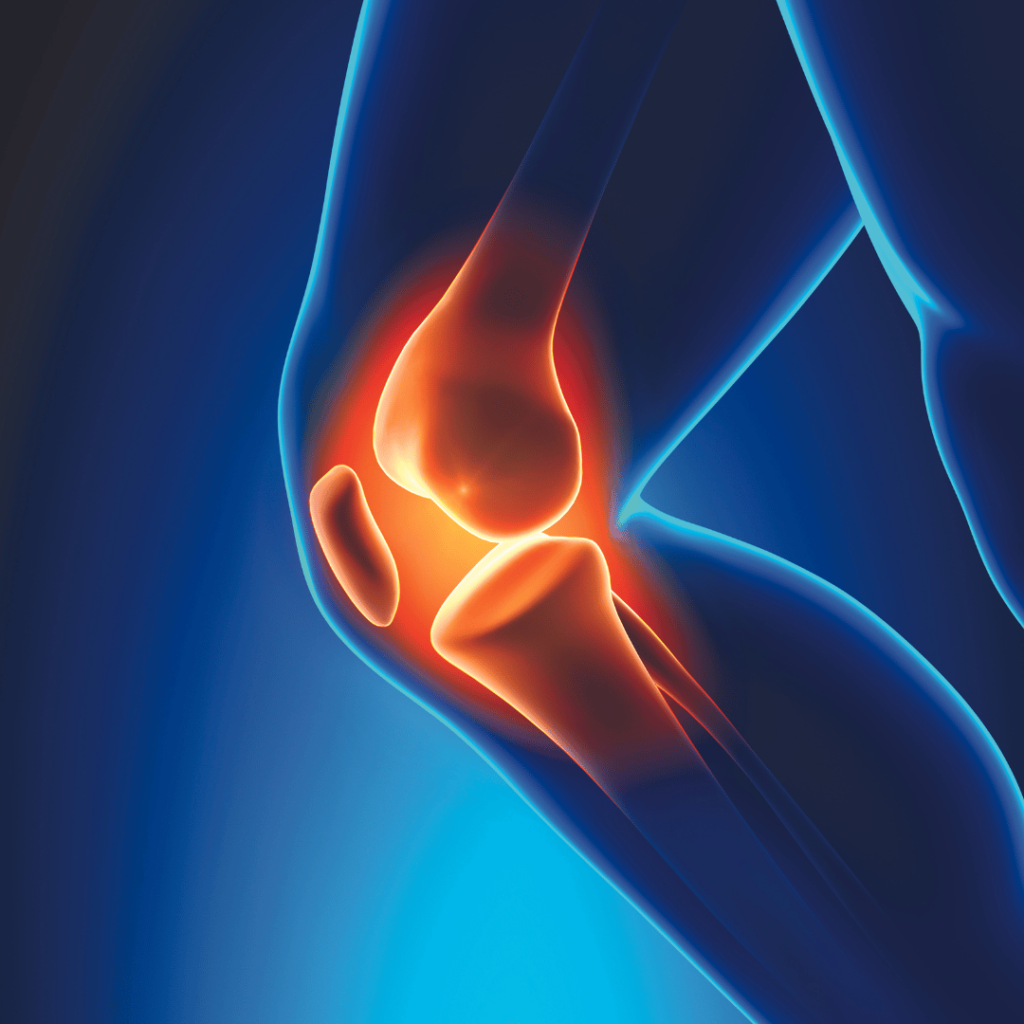

Osteoarthritis

GFC therapy represents an exciting breakthrough in the treatment of osteoarthritis. It harnesses the body’s natural healing capabilities by utilizing concentrated growth factors to stimulate tissue repair and regeneration. These growth factors, obtained from the patient’s own blood, are injected into the affected joint, targeting damaged tissues and promoting the formation of new cells. Unlike traditional treatments, GFC therapy aims to address the underlying causes of osteoarthritis, offering the potential for long-term relief and improved joint function.

Clinical studies and patient testimonials have shown promising results regarding the effectiveness of GFC therapy in relieving knee pain associated with osteoarthritis. The growth factors injected into the affected joint stimulate the body’s natural healing response, promoting the repair of damaged tissues and reducing inflammation.

Furthermore, GFC therapy has demonstrated the potential to slow down the progression of osteoarthritis. By targeting the underlying causes of the disease, it may help to preserve joint function and delay or even avoid the need for more invasive interventions like joint replacement surgery.